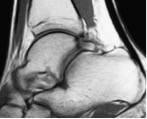

Os Trigone

Cette ossification (non systématique) au niveau de la partie postérieure du talus peut être traumatisée lors des mouvements d’hyper flexion plantaire de la cheville.

Le bilan d’imagerie doit être complet pour valider la lésion (radio, scanner et IRM).